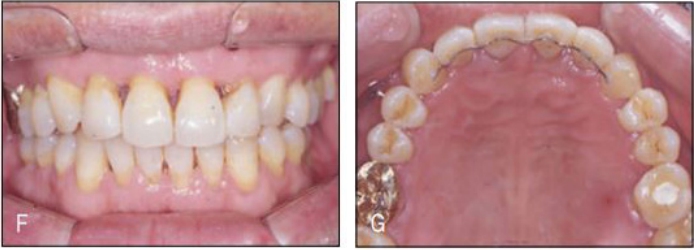

[증례] 치주질환으로 심한 병적 치아이동(pathologic tooth migration, PTM)이 나타나 기능적, 심미적 회복을 위해 교정을 한 65세 고령 환자 증례. 전악 치근단사진에서 볼 수 있듯이 전치 뿐 아니라 구치부 전 치아에 걸쳐 심한 염증이 발생하고 이로 인해 구치부에서도 PTM 이 심하게 나타나 치주치료 후 구치 교합이 불안한 상태가 초래 된 환자이었다.

치주치료 후 보철의사에게 돌아온 환자의 교합을 보고 dual bite 상태에서는 보철을 할 수 없는 바, 치주질환 이전의 교합 상태로의 교정을 의뢰하였다. 전체적으로 치주지지가 불량하여 움직일 치아만 제대로 움직 이는 치료가 매우 어려운 케이스이기 때문에 기공비용이 다소 많이 들지만 간단하게 치료 할 수 있는 투명교정장치를 사용하여 치료하기로 하였다. 구치부의 경우 협측전위된 우측 제1, 제2소구치와 좌측 제1소 구치 이동을 위해 투명교정장치를 사용할 경우 다수의 장치가 필요할 것으로 생각되어 대구치를 고정원으로 하여 소구치를 간단 하게 이동시키는 TPA 장치를 이용하였으며, 이후 투명교정장치로 전치부 공간을 클로져하여 간단하게 교정을 마무리 하였다(그 림 23-5, 6).